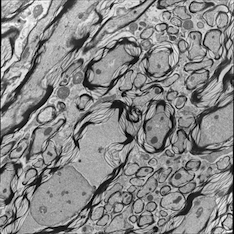

For image analogies based image registration, I have corresponding TEM/Confocal Microscopic image pairs of mouse brains with corresponding regions highlighted by a box. Using the correlative microscopy technique on the mouse brain, I want to localize specific brain regions associated with Pelizaeus-Merzbacher Disease (PMD) and do quantitative assessment of hypomyelination and demyelination in mice. PMD is one of a group of genetic disorders characterized by progressive degeneration of the white matter of the brain affecting the myelin sheath, the fatty covering that acts as an insulator on nerve fibers in the central nervous system.

The confocal microscopy images are multichannel color images in our test dataset. The blue channel is based on the blue stain DAPI (a fluorescent stain) which stains the DNA of the cell nucleus and corresponds to dark regions within the nuclei in the TEM. The green channel is based on the stains of the myelin sheats, visible as dark black layers covering the neurons in the TEM images. The red channel is not explicitly stained for and is caused by the auto-fluorescent effect of lipofuscin. The confocal image with RGB channels and its corresponding TEM image are shown in Fig. 5.

Currently I have six pairs of 2D TEM/confocal images with resolutions 582.24 pixels per μm𝜇𝑚\mu m and 7.5887.5887.588 pixels per μm𝜇𝑚\mu m respectively (1μm=1micron=106m1𝜇𝑚1𝑚𝑖𝑐𝑟𝑜𝑛superscript106𝑚1\,\mu m=1\,micron=10^{-6}\,m). The resolution is different between two images and only a small region in the confocal image corresponds to the TEM image.

(f) TEM image

Figure 5: Example of Confocal image with RGB channels and TEM image